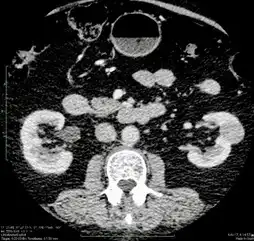

Η διάγνωση πραγματοποιείται με αξονική τομογραφία μετά τη χορήγηση ενδοφλέβιου σκιαγραφικού. Η πρόσληψη του σκιαγραφικού από τον όγκο είναι χαρακτηριστική της νόσου. Η αξονική τομογραφία (CT) μας δίνει πληροφορίες για το μέγεθος του όγκου, πιθανή έξωνεφρική επέκταση, τη συμμετοχή ή μη του σύστοιχου επινεφριδίου, ύπαρξη λεμφαδένων και την κατάσταση του άλλου νεφρού. Οι όγκοι του νεφρού μπορούν να διαχωριστούν βάσει της εικόνας τους στην CT. Οι όγκοι μπορούν να είναι συμπαγείς ή κυστικοί. Για την αξιολόγηση των δεύτερων χρησιμοποιείται το σύστημα Bosniak.

Σε περιπτώσεις που υπάρχει επιδεινωμένη νεφρική λειτουργία ή αλλεργία στο σκιαγραφικό ή θέλουμε να διαγνώσουμε πιθανή ύπαρξη θρόμβου στη νεφρική ή την Κάτω Κοίλη Φλέβα, χρησιμοποιείται και Μαγνητική Τομογραφία. Συμπληρωματικά στη σταδιοποίηση του καρκίνου πρέπει να διενεργείται CT στον θώρακα για τον αποκλεισμό πνευμονικών μεταστάσεων, ενώ δεν θα πρέπει να παραλείπεται η διενέργεια ακτινογραφίας θώρακας. Άλλες εξετάσεις όπως σπινθηρογράφημα οστών, CT εγκεφάλου, PET scan διενεργούνται εφόσον υπάρχει η αντίστοιχη συμπτωματολογία.